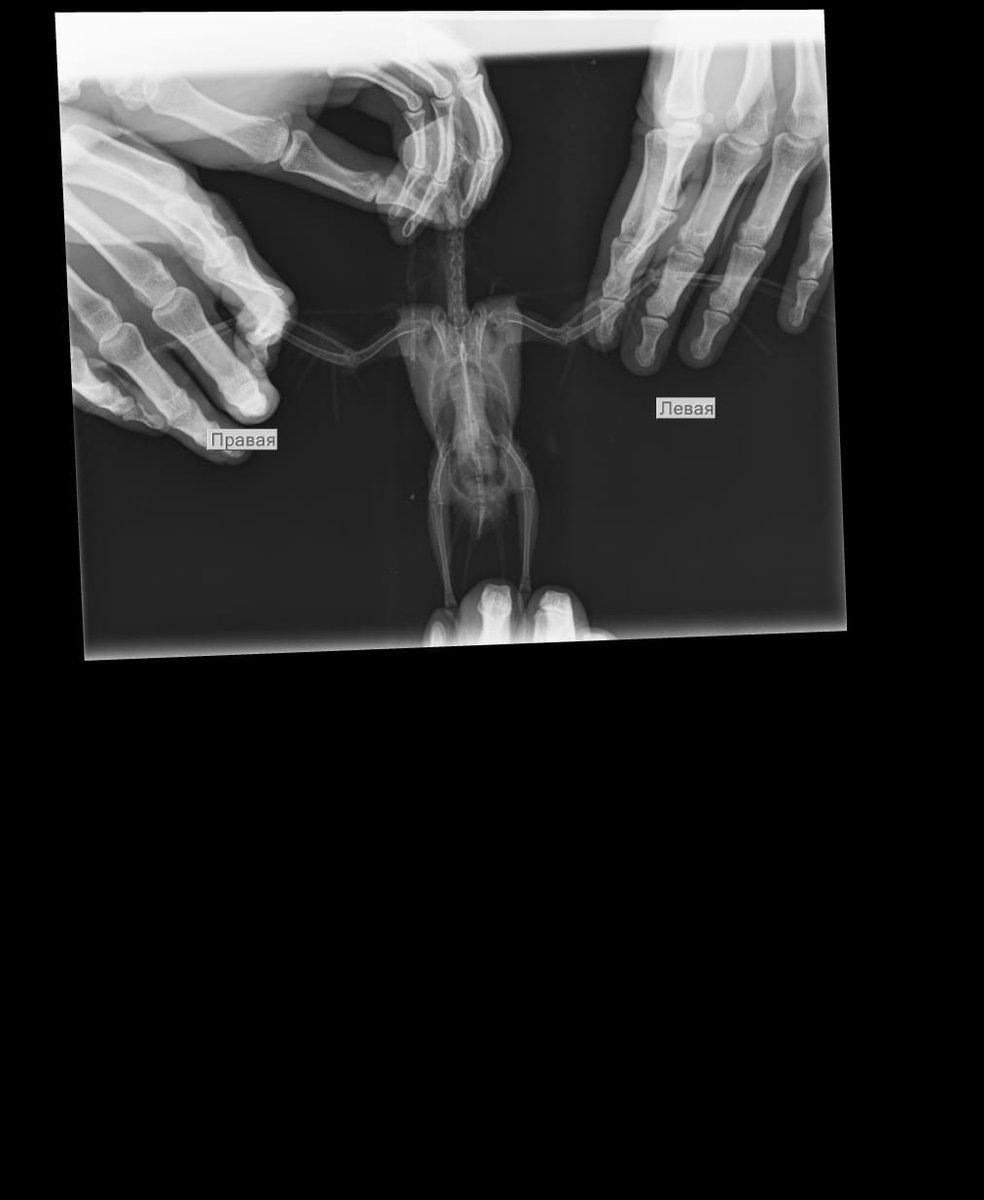

начали сдавать анализы дальше. и сделали рентген. По рентгену - воспаление воздухоносных мешков, пневмония, увеличение границ печени (наверное, я перелечил ее).

IMG-20201020-WA0007.jpg

У птицы в крови завышена щелочная фосфатаза. на рентгене - пневмония и воспаление воздухоносных мешков. Птица прикрывает глаза, при этом издает звуки клювом (или из носоглотки они идут), видно, что чешет клювом в в этот момент. Что это? Помогите пожалуйста. Птица более более полугода, с момента покупки.